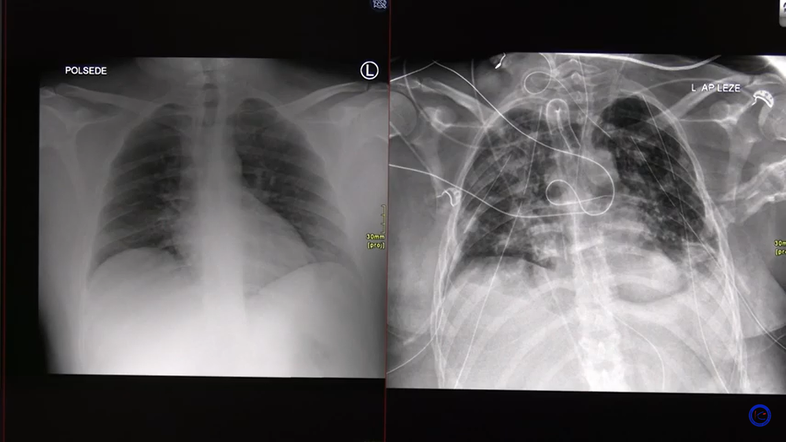

Na drugem posnetku pa Turel opisuje zelo težko obliko covid-19 pljučnice pri 30-letniku, ki se je končala s presaditvijo pljuč.

Kot pojasni, je bolnik nekaj dni po okužbi začel težko dihati, zato je prišel v bolnišnico. Na rentgenskem posnetku sprva ni bilo videti kakšnih bistvenih sprememb. Vendar je bila očitno povzročena tako akutna okvara, da ga je bilo kmalu treba priklopiti na respirator, je povedal. Pljuča so bila v celoti megličasta, zaradi okvare je prišlo do razpoka pljuč, kar po besedah zdravnika ni ravno redek pojav. Stanje se je še naprej slabšalo, po treh dneh so pljuča postala povsem bela, niso bila več sposobna izmenjavati kisika iz okolja, niti s pomočjo respiratorja, zato so morali bolnika priklopiti na izventelesno membransko oksigenacijo. Vendar se pri tem bolniku pljuča niso dobro popravljala, zato je bila potrebna presaditev. Nekateri bolniki to fazo prebrodijo tudi brez presaditve, je povedal strokovnjak.

Turel je nato pokazal presajena pljuča, sicer utrujena od presaditve, vendar funkcionalna. Bolniki, ki so preboleli tako hudo obliko covida-19, niso bili prizadeti le na pljučih, na dolgotrajnem zdravljenju oslabijo mišice, shujšajo, po presaditvi pljuč pa je potrebna kar dolga rehabilitacija. Življenje po njegovih besedah ni povsem enako kot pred presaditvijo, vendar se lahko bolniki funkcionalno popravijo, čeprav morajo še vedno jemati zdravila proti zavrnitvi organa, ki niso brez stranskih učinkov. Turel je bolnika poklical pred nekaj dnevi in izvedel, da vsak dan prehodi že več kot tri kilometre in se postopoma privaja na novo življenje.